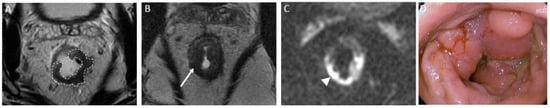

4.4.4. Mucinous Rectal Cancer